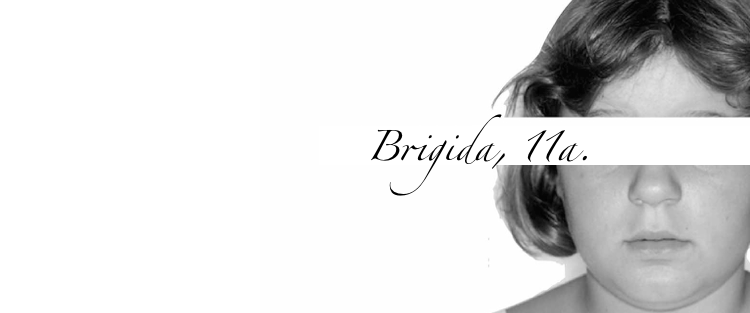

Nome

Brigida

Età

11